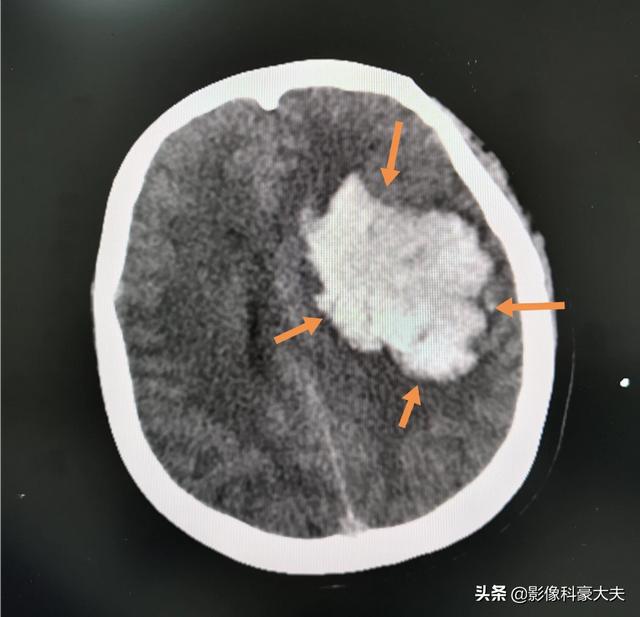

この中年女性のように、何年も薬を飲まずに高血圧を患っていたが、突然昏睡状態に陥り、CTで大量の脳出血と診断された。

このようなケースでは、血腫を除去して頭蓋内圧を下げる手術をすれば、命を救うことができる場合もあるし、少し障害が残る程度で、基本的には自分のことは自分でできる。しかし、中にはうまくいかず、植物状態になることもある。

もう少しがんばって闘うことを選ぶ家族もいれば、治療を見送ることを選ぶ家族もいるだろう。何が正しいのか、何が間違っているのかを評価するのは難しい。